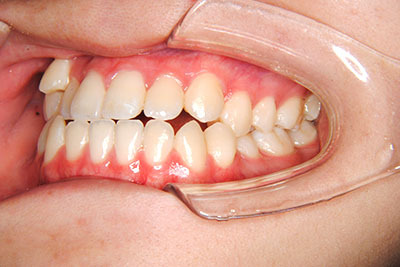

小学生高学年や中高生で矯正治療を考えている方へ

歯が乳歯から永久歯に生え変わった小学生高学年や、中高生でも矯正治療に手遅れということは全くありません。

成長中の顎の骨を矯正できたり、この時期の矯正はおとなになってから矯正治療を始めるよりも短期間で済むことがほとんどです。当院だとおおよそ1年で動的治療(マルチブラケット装置をつける期間)が終わることが多いです。